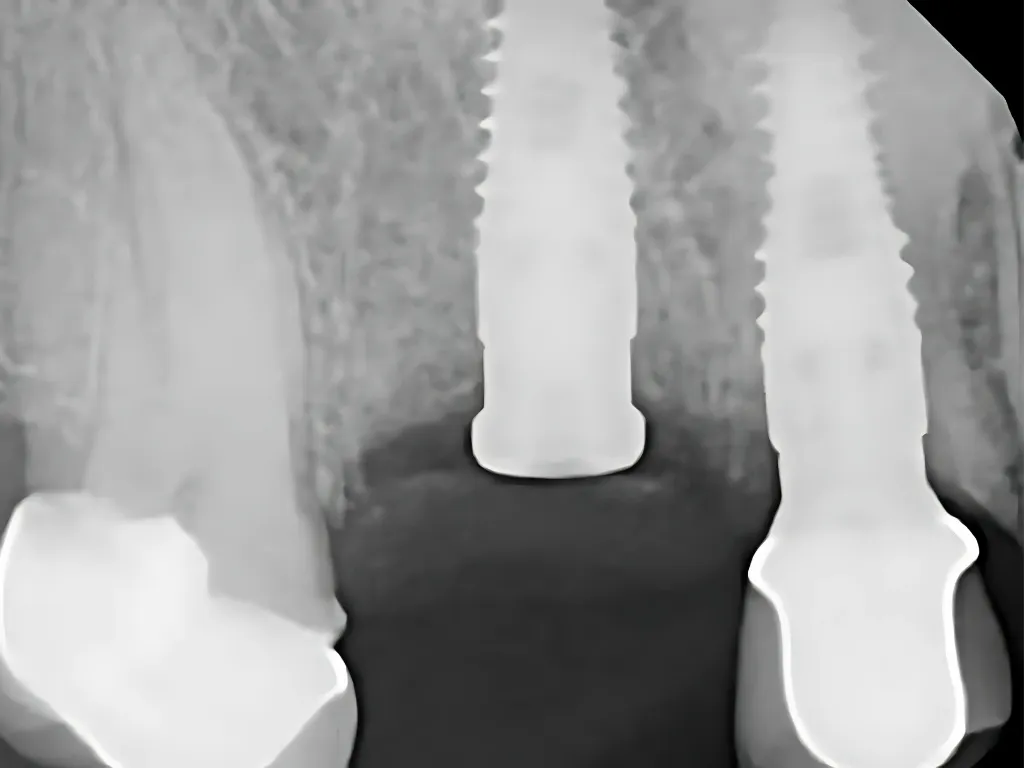

Assessment of Crestal Bone Loss and Degree of Success

İmplantasyon ve protetik yükleme sonrası osseointegrasyon başarısı ve ilk yıl sonunda oluşan krestal kemik kayıpları